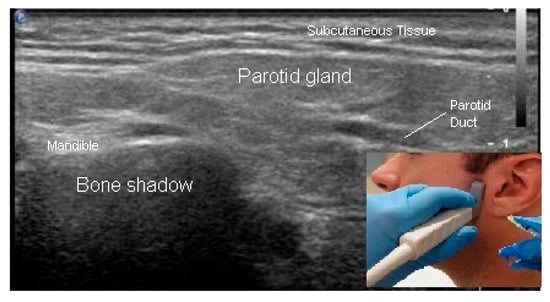

- In Plane Technique (IPT). When using an IPT the needle is inserted along the length of the transducer (Figure 6b and Figure 7a). With the IPT, the entire needle and its tip is visualized, an advantage over the OPT. However, this technique can be challenging to perform because the sonographer must keep the needle within the narrow US beam. Another challenge is that optimal needle visualization requires that the needle be inserted and maintained in an orientation perpendicular to the US beam Figure 8a. When inserted at a steep or oblique angle, visualization of the needle may be lost due to needle anisotropy [24,50,54] (Figure 8b).

- Anisotropy is one of several important artifacts encountered during US imaging, others being posterior acoustic shadowing, posterior acoustic enhancement, and reverberation. Anisotropy is a characteristic of some tissues/structures (like tendons) and of needles, whereby the reflection of soundwaves from the tissue or structure is affected by the incidence angle of the soundwaves. When soundwaves are perpendicular to the structure, the structure can be visualized in its entirety but visualization of the structure is compromised or lost at other angles [50,54,55,56,57].

- To keep the needle perpendicular to the US beam requires needle insertion to be at a flat angle relative to the transducer (Figure 8a). For superficial structures, such as the sternocleidomastoid muscle, this is easily accomplished. When targeting deeper muscles/structures, the needle must be inserted at some distance from the transducer to maintain an angle that minimizes anisotropy. This often requires a larger gauge, longer needle.